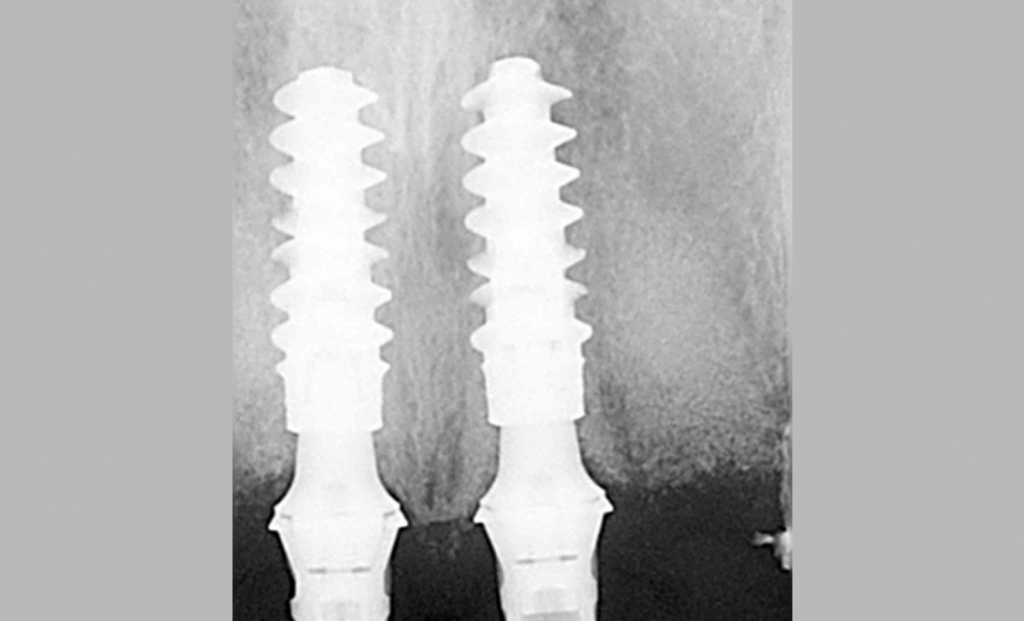

Этот пациент обратился ко мне с жалобами на сильную боль, покраснение и отек вокруг только что установленной коронки на имплантате. В анамнезе было следующее: был снят аналоговый оттиск с уровня имплантата и отправлен в лабораторию для изготовления коронки. У лаборанта не было указаний относительно расположения шейки имплантата по отношению к мягким тканям и кости.

Была выбрана самая короткая высота десневой манжеты (GH), так как она является наиболее безопасной с эстетической точки зрения, поскольку металлическая кромка не будет видна над десной. При доставке коронки на имплантат стоматолог столкнулся с трудностями при «посадке» коронки на абатмент.

Коронка была установлена со значительным сопротивлением для достижения необходимого значения торка. Ущемление твердых и мягких тканей из-за очень острого профиля выступа вызывает давление на кость, что приводит к некрозу и, в конечном итоге, к потере маргинальной кости в этой области. Чтобы избежать подобных осложнений, необходимо выбирать правильный абатмент.

На основе ОПТГ, сделанного после установки или имплантата (рис. 2), стоматолог может выбрать подходящую высоту десневой манжеты для абатмента и направить техника, предоставив рентгеновский снимок и/или спецификацию формирователя десны. Большинство систем имплантатов имеют синхронизированные формы и контуры хирургических абатментов и компонентов протеза.